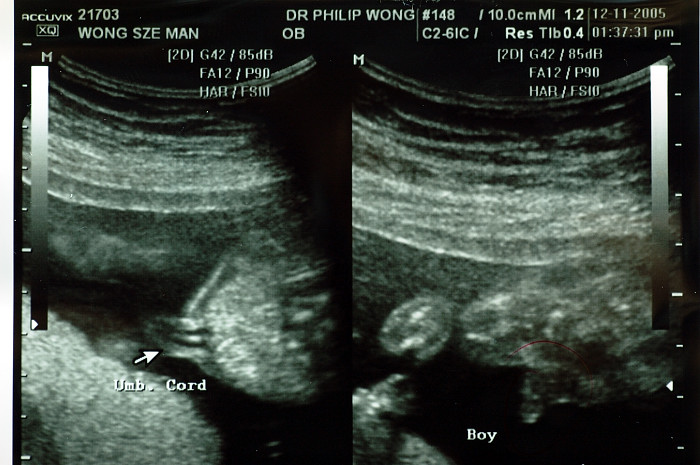

我太座19W3D去照收1000蚊呀 重照到呢D野

照左安心D o既,睇哂全身,俾我D相你睇下丫,好鬼開心架

http://www.fotop.net/CCP2005/121105detal<----更多相片請按入去丫